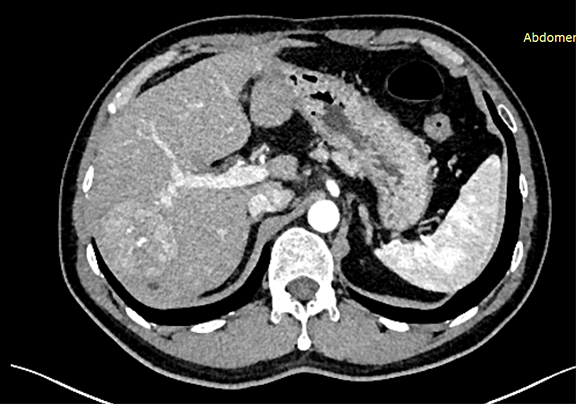

下腹部增强CT示:符合肝脏术后改变,请结合临床;肝右叶占位性病变,考虑肝Ca 可能性大。

术前CT检查:

动脉期